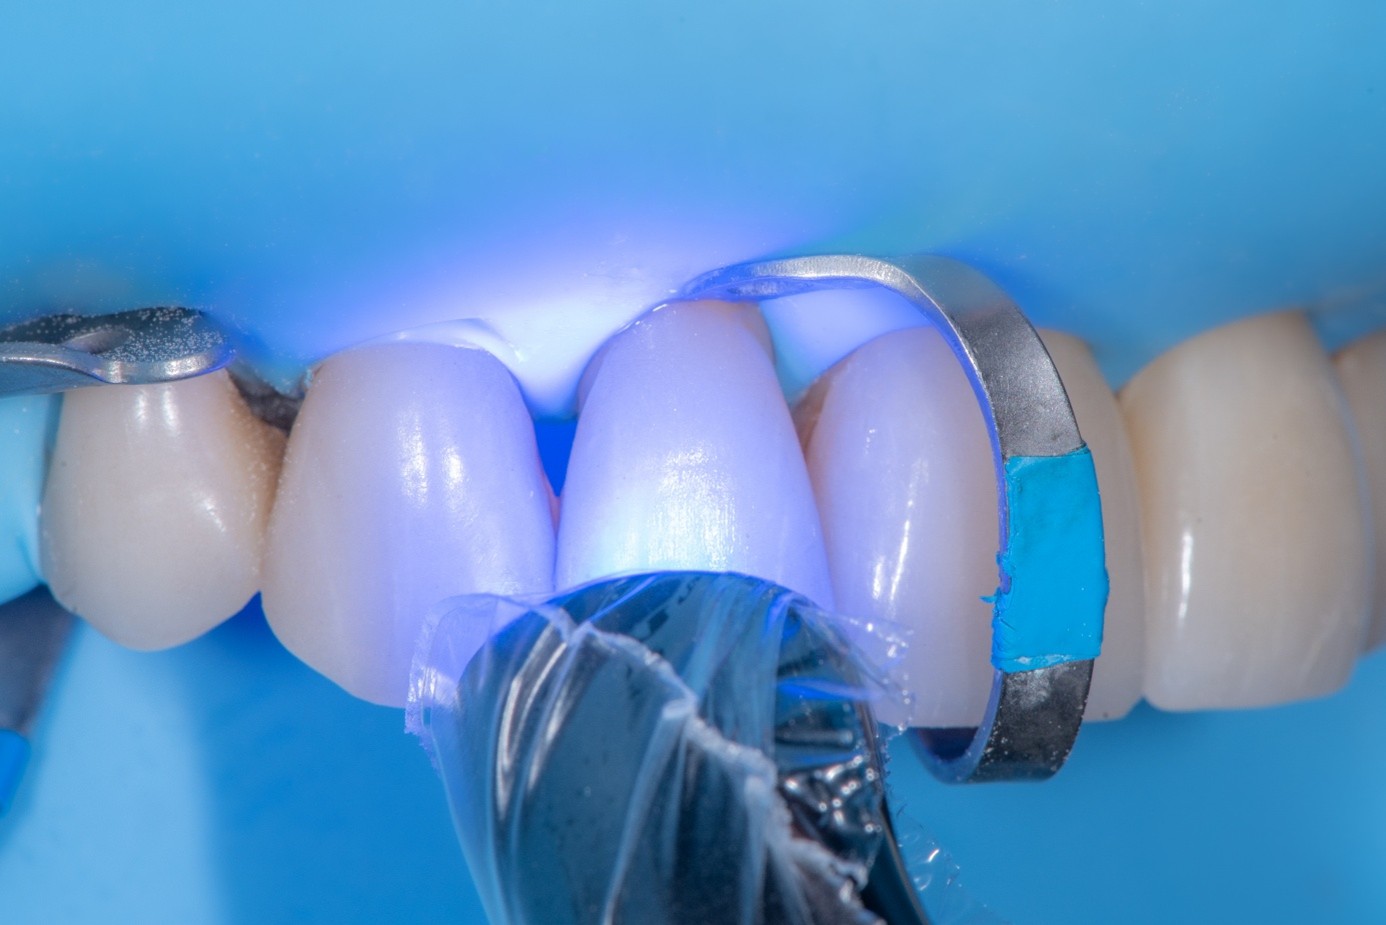

(30.) Intraoral view after absolute isolation with a rubber dam, showing the prepared tooth surface cleaned and roughened with sandblasting, ready for adhesive application and bonding to the crown.

Figure 30